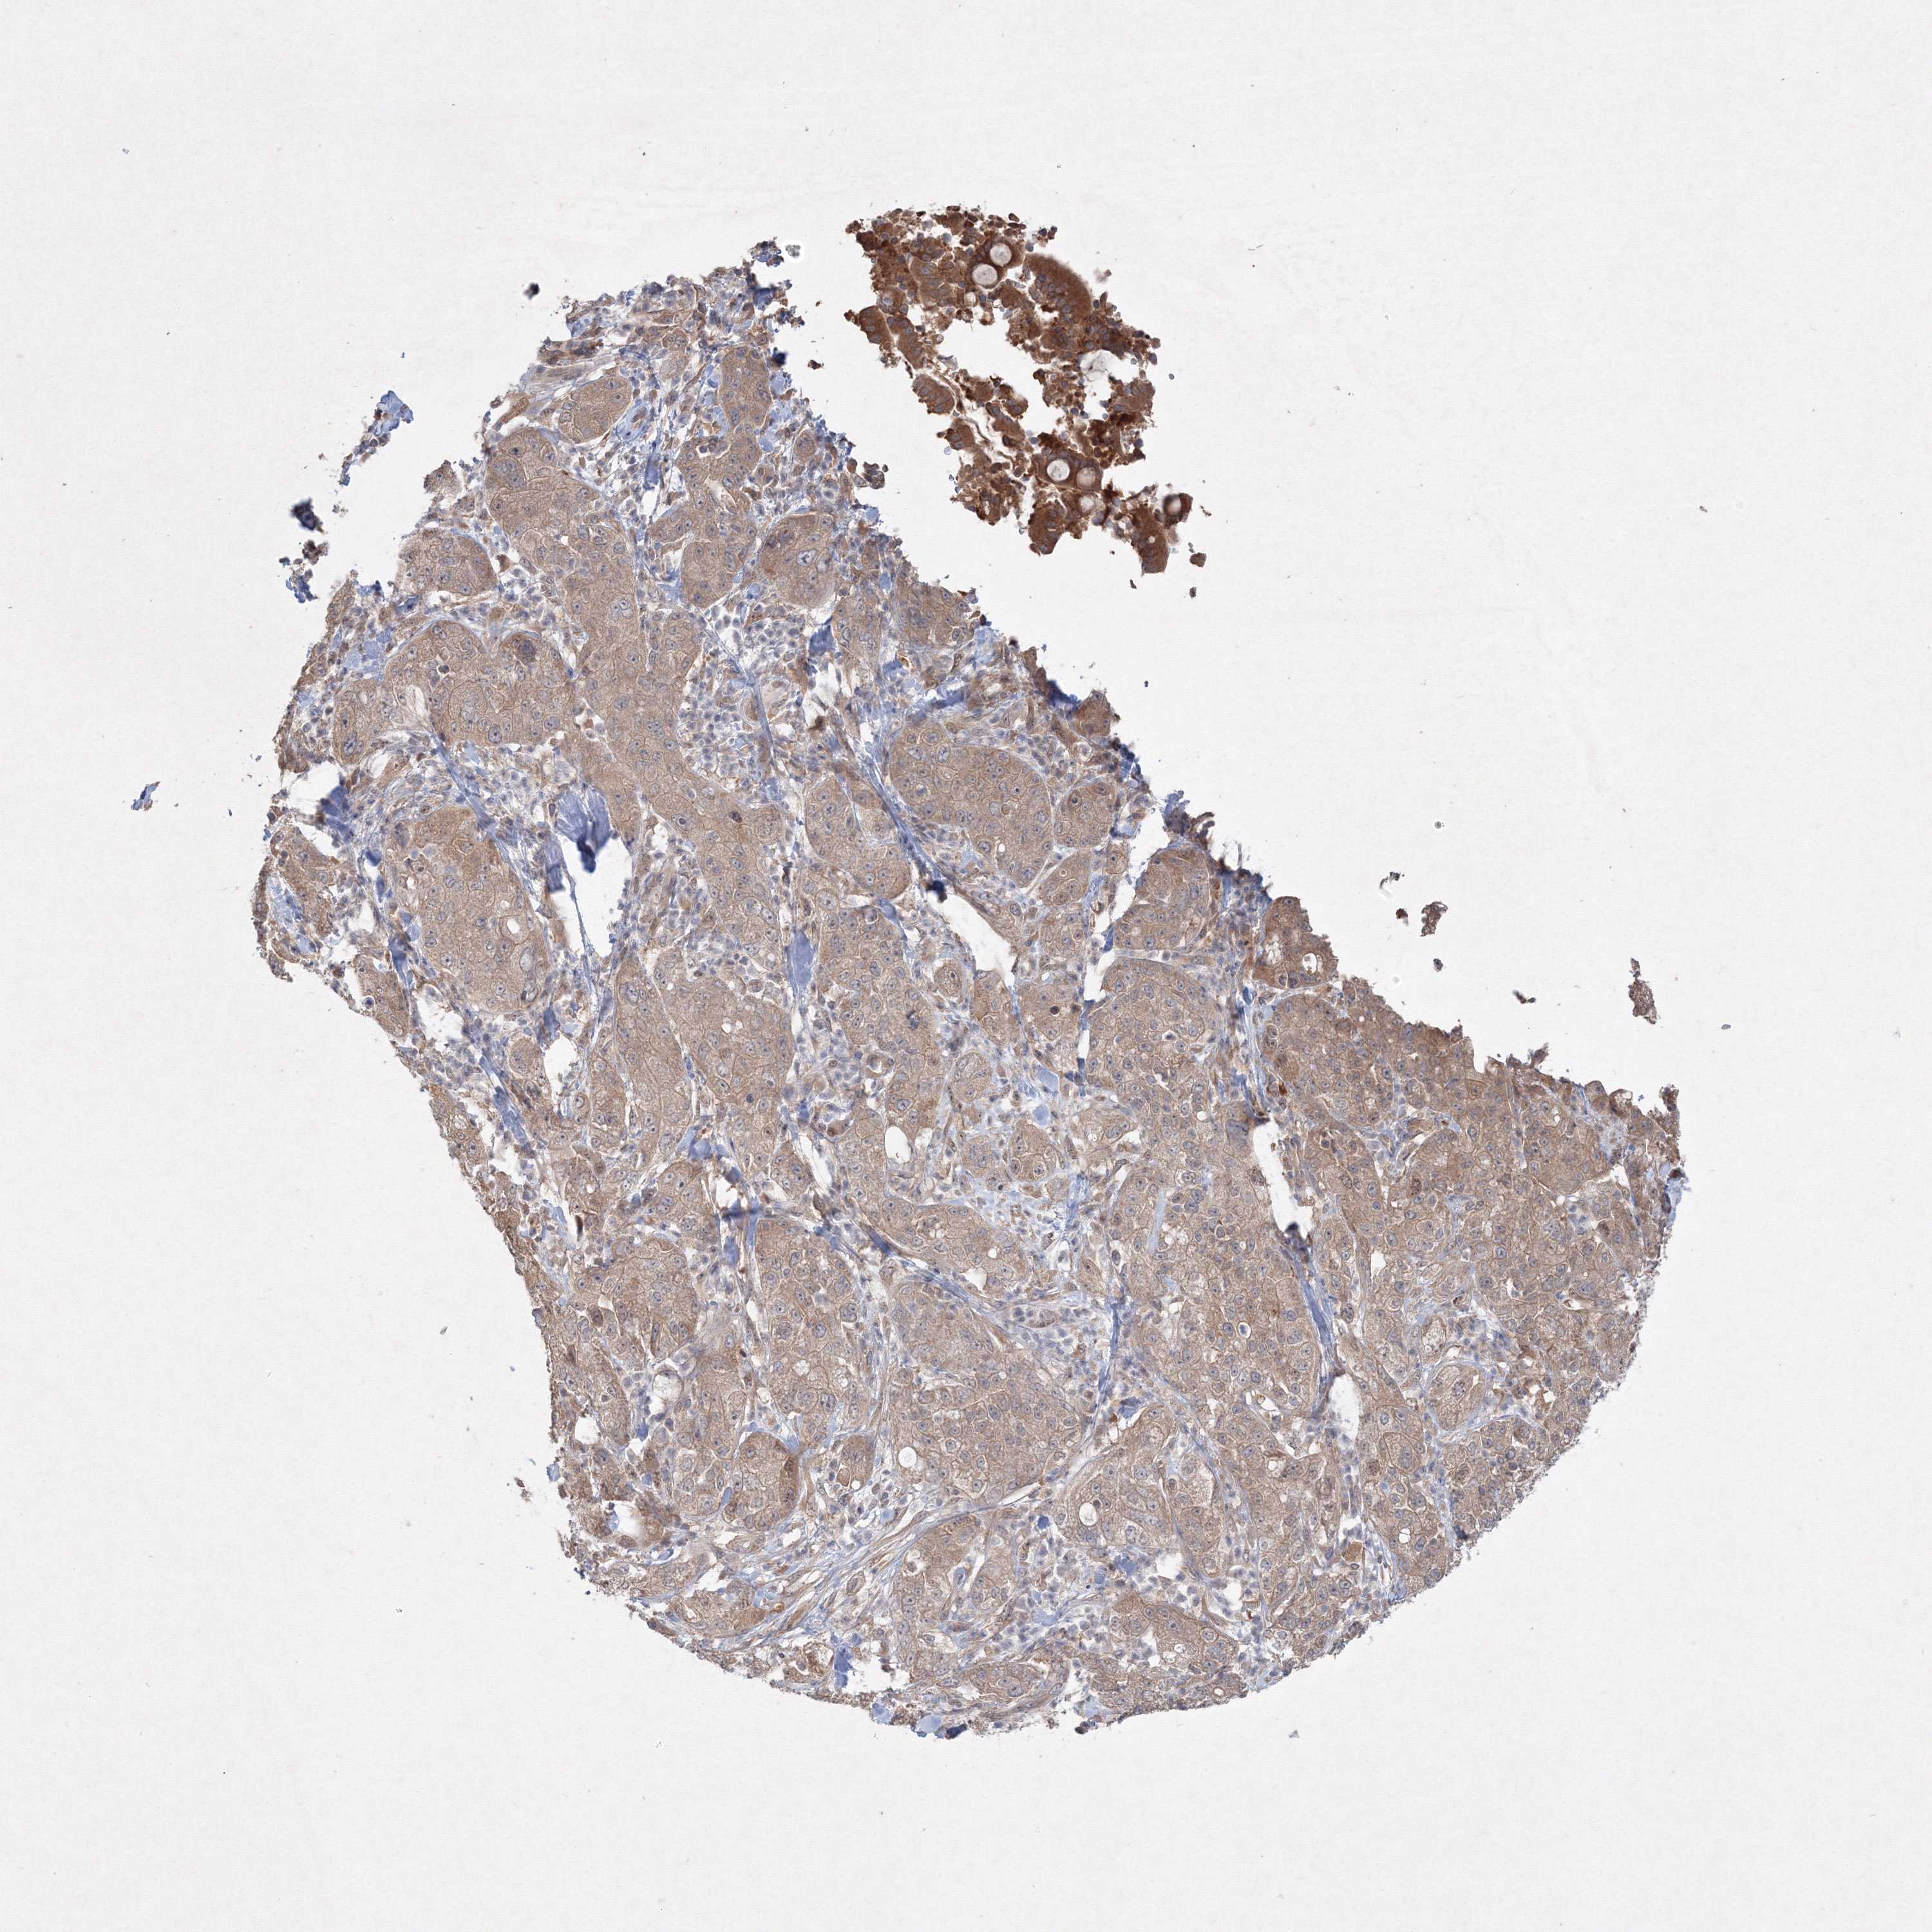

PANCREATIC CANCER - Protein expressioni

A mouse-over function shows sample information and annotation data. Click on an image to view it in a full screen mode. Samples can be filtered based on level of antibody staining by selecting one or several of the following categories: high, medium, low and not detected. The assay and annotation is described here.

Note that samples used for immunohistochemistry by the Human Protein Atlas do not correspond to samples in the TCGA dataset.

Antibody stainingi

Antibody staining in the annotated cell types in the current human tissue is reported as not detected, low, medium, or high, based on conventional immunohistochemistry profiling in selected tissues. This score is based on the combination of the staining intensity and fraction of stained cells.

Each image is clickable and will lead to virtual microscopy that enables deeper exploration of all samples and also displays staining intensity scores, fraction scores and subcellular localization as well as patient and tissue information for each sample.

Antibody HPA030943

Antibody HPA030944

Antibody HPA030945

Antibody CAB034184

Staining

High

Medium

Low

Not detected

Intensity

Strong

Moderate

Weak

Negative

Quantity

>75%

75%-25%

<25%

None

Location

Nuclear

Cytoplasmic/membranous

Cytoplasmic/membranous,nuclear

Adenocarcinoma, NOS